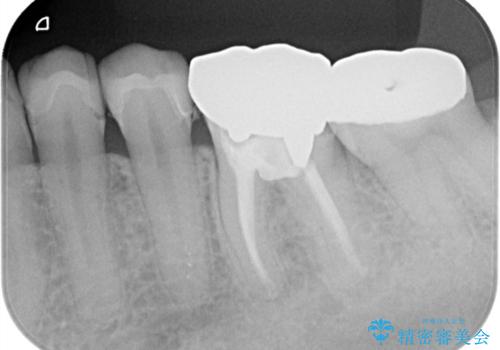

- 主訴:銀の詰め物が何本か入っているので白くしていきたい

保険適用のメタルインレーのやり替え希望だったため、審美性・適合性の良いセラミックインレーでのやり替えとなりました。

メタルインレーを除去したところ、二次カリエスうを確認したため除去・CR裏層の後、形成・印象しています。

セラミックインレーの接着操作時にはラバーダム防湿を行っています。